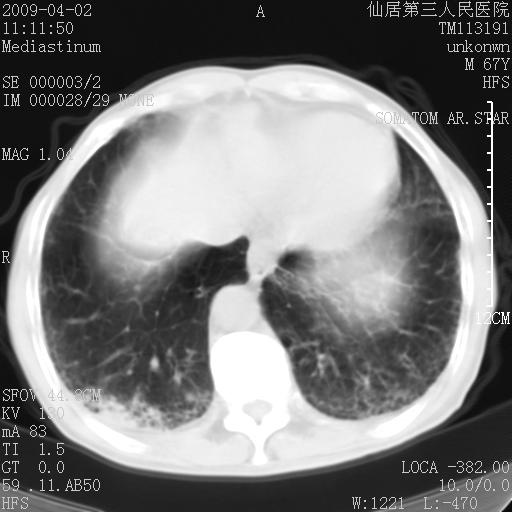

患者老年男性,乏力畏寒来诊,摄胸片示右下肺感染性病变,抗炎两周后复查胸片,无好转有进展。

后做ct平扫表现如下:

考虑右肺炎症可能性大,不除外细支气管肺泡癌

是否还要考虑肺间质纤维化,建议hrct扫描。

考虑间质性肺炎。

病灶呈蜂窝征,纵隔多个淋巴结肿大;肺泡癌需考虑

我认为普通的感染应该可以除外,间质性肺炎可能性较大,但如何解释纵膈的淋巴结肿大呢

考虑双肺间质性改变(间质纤维化?)伴右肺下叶感染。